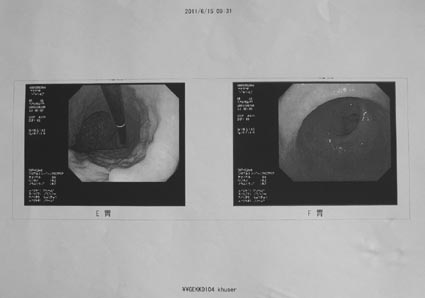

2011年6月6日

血液検査及び内視鏡による検診結果

2)上部内視鏡

十二指腸にポリープ在り、その他異常なし

<所見> 上部臓器に問題個所はなし